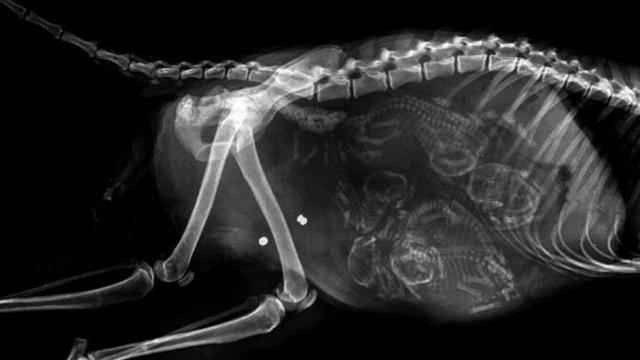

1.猫咪的 , 天撸了!密密麻麻的好多!